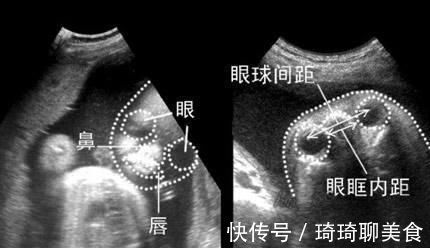

文章插图

胎儿体位导致的

胎儿做四维彩超的时候,一般不会直接将正脸对着我们,我们看到的多是侧面图像,但是为了更清晰的判断鼻子、嘴唇等面部的结构,会尽量合成一个正面的图像,合成过程中出现了失真的情况,导致鼻子比实际要大。